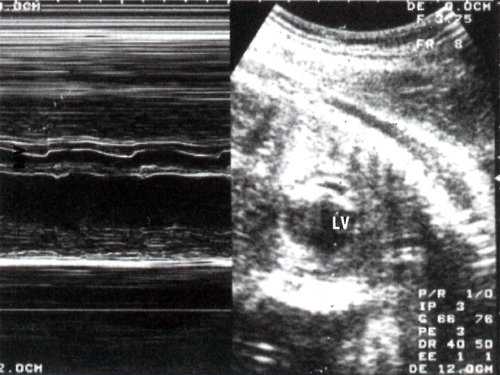

Сократимость миокарда левого желудочка значительно изменена: амплитуды сокращения и диастолического расслабления представлены практически в виде прямой линии (рис. 2).

Рис. 2. В и М-сканирование на уровне поперечного сечения левого желудочка сердца плода 24 недель гестации . Отмечается значительное уменьшение амплитуды раскрытия створок митрального клапана. LV - увеличенный левый желудочек.